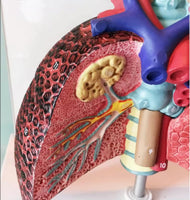

Modelo cardiopulmonar sistema respiratorio laringe

El modelo cardiopulmonar muestra Laringe humana, modelo pulmón cardiopulmonar, corazón, laringe, tráquea, nodos linfáticos, caja torácica médica